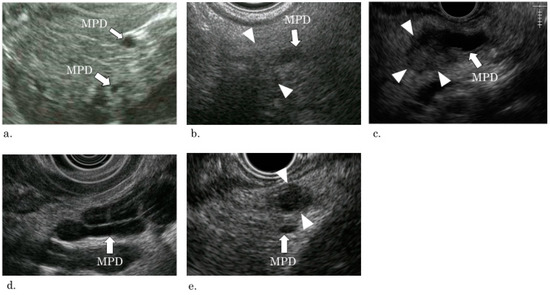

3. Classification of EUS findings

- A1: Simple stricture type—an MPD was strictured without any other findings;

- A2: Hypoecho stricture type—a strictured part was surrounded by a focal hypoechoic area without clear demarcation;

- A3: Tumor stricture type—a tumor with clear demarcation was recognized in the strictured part.

- B: Dilation type—an MPD or a branch duct was dilated without a downstream stricture;

- C: Parenchymal tumor type—a pancreatic tumor with clear demarcation located apart from the MPD.